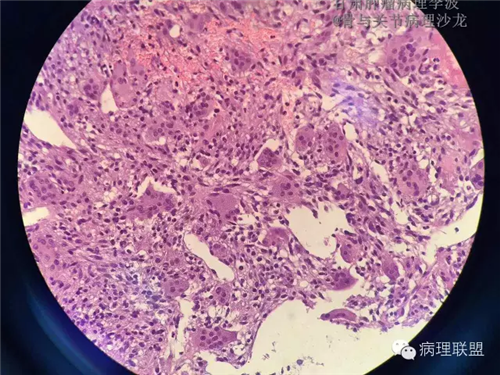

M/14 骶骨骨肉瘤-张惠箴讲解

病例由甘肃肿瘤病理 李波 提供,致谢。